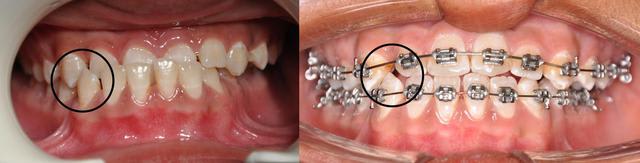

Concernant l’occlusion croisée à gauche, il y a deux problèmes : un problème vertical d’égression à partir des canines et un problème transversal.

Corrige d'abord le problème vertical, l’occlusion croisée sera ensuite relativement facile à traiter avec de simples élastiques.

les dernieres photos du cas

- Qu'attends-tu pour fermer les diastèmes en bas ? Il me semble que cela diminuerait la vestibuloversion des incisives supérieures.

- La 4ème photo n'est pas exacte, ton patient à latéroglissé à gauche. Tu l'as prise comme ça volontairement ?

- Tu cherches toujours une solution pour ton problème d'occlusion croisée ?

**non, c’est une photo avec miroir qui montre bien les rapport molaires et canines et qui montre le début de la correction de l’articulé en jouant sur le sens transversal de l’arc niti

**oui, je cherche à traiter le coté gauche sans modifier le coté droit

En faite j’ai peur que les élastiques criss-cross me créent une Latérodéviation de la mandibule

Pour moi la mandibule est correcte dans le sens transversal et le problème se situe au niveau du coté maxillaire gauche

Il ne s'agit pas de faire confiance ou pas a l'examen clinique de notre ami(e)takamatika. Il s'agit d'une erreure tres ferequente que chacun de nous pourrait la faire surtout si la musculature a bien enregistrer cette deviation associee peut etre a une relle laterognathie. Je maintiens quand-meme mon point de vue car entre les deux series de photos (on ne sait pas combien de temps entre les deux), mais l'articule inversee au niveau de la canine inferieure/laterale sup cote droit a bien disparu, l'inverse d'articule anterieur n'est plus la et les lignes medianes dentaires se sont alignees!

Dans ce cas il y a une choses des deux: Soit la situation de depart etait en RC et le recentrage dentaire va creer un decentrage articulaire et comme disait ceramik les ATM n'aiment pas cette situation, ou bien (et c'est ce que je pense) la situation initiale etait en occlusion de convenance due a un contact premature au niveau de la canine/laterale et le simple fait de supprimer ce contact par le nivellement denatire a permis a la mandibule de se recentrer. Si des nouvelles radios de profil et de face sont a faire maintenant on ne doit pas voir le meme decalage condylien de depart et on peut quantifier le probleme d'origine squelettique.